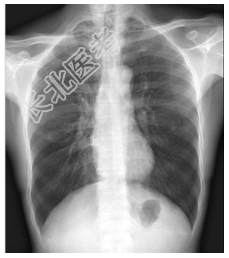

- [材料题] 患者,男性,70岁,秋冬季咳嗽、咳痰3年余,胸闷、气促2天入院。查体:桶状胸,双肺呼吸音粗,未闻及干、湿性啰音。心脏体查无异常。做胸部X光平片检查。

- 简答题1、诊断及依据是什么?

- 简答题2、鉴别诊断有哪些?